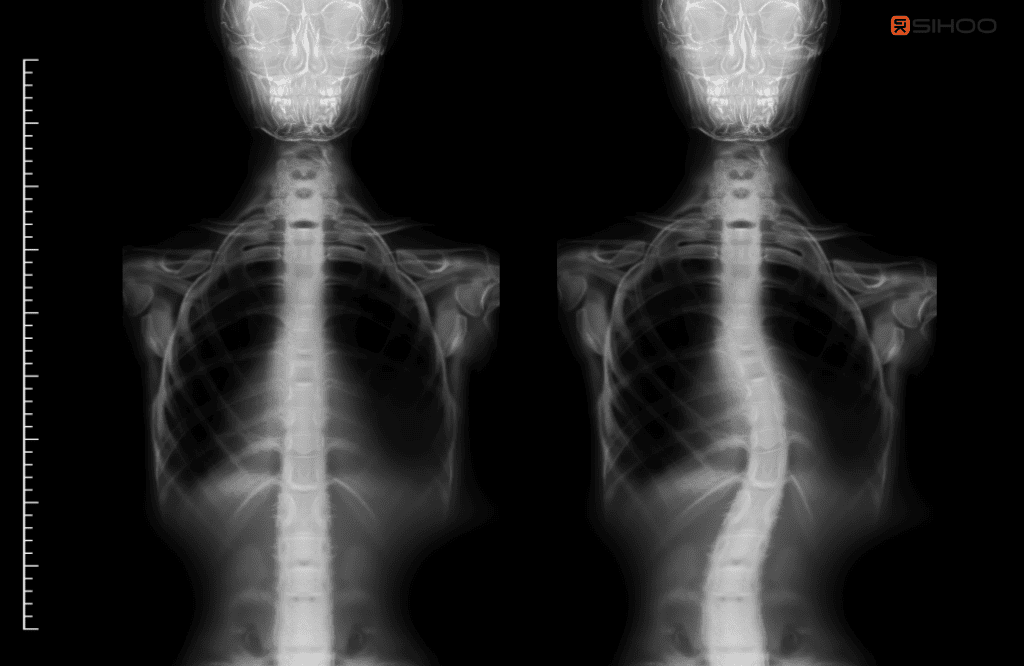

What is scoliosis?

Scoliosis is when the spine curves and twists to one side. It can affect people of any age. It often starts between 10 and 15 years old, but adults can have it too. Signs may include uneven shoulders or hips and back ache. Treatment depends on age and how severe the curve is; mild cases may simply be monitored.